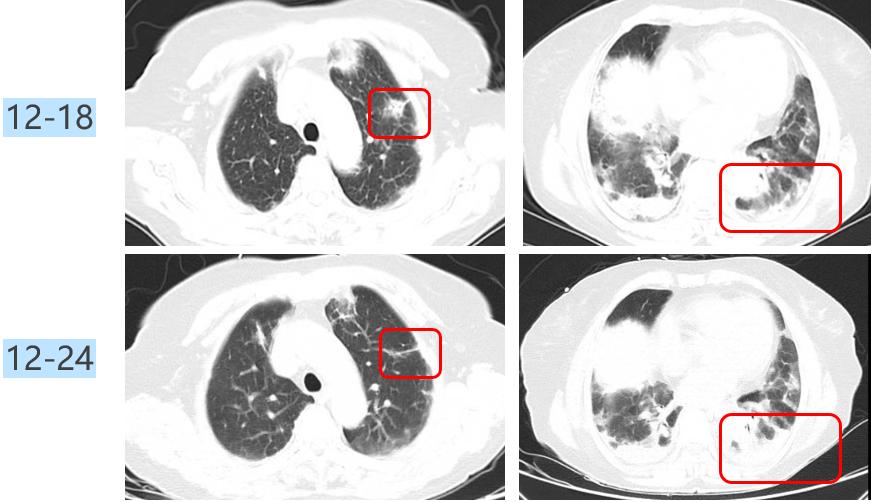

病例: 74岁女性咳嗽咳痰伴气短1月余,已经有亚急性过程了,1月前无明显诱因出现咳嗽,伴喘鸣音,白痰,不易咳出,活动后气短。当地抗感染治疗效果不佳。实验室检查:血常规 WBC 4.52*10^9/L,LY# 0.93*10^9/L,NE% 72.3%。虽然感染指标并不高,但两肺有多发病变。

胸部CT示(12-18):两肺多发斑片絮状影,右中肺及两下肺实变,考虑感染可能。

治疗中患者的氧合指数仍然在快速下降,我们复查CT,显示大部分病变在进展。

图:胸部CT(12-24):两肺纹理增多,两肺门影增浓,两肺野内多发斑片影,较前2021-12-18部分稍有好转,部分稍明显。

仔细比对后,我发现有一个病灶吸收了,机化性肺炎?气管镜下并没有明显感染的征象,后来,NGS只检出纹带棒状杆菌7个序列、光滑念珠菌16个序列,载量很低,而且这两个病原体本身就存在于呼吸道,所以我将它们定义为阴性。

这时进行治疗调整:2021.12.24-12.26:比阿培南0.3g q6h+替加环素 100mg q12h+甲强龙 120mg qd;12.27-2022.01.02:哌拉西林他唑巴坦4.5g q6h+甲强龙 40 mg qd。激素加量、抗生素两天后减量了。治疗效果体现在氧合指数上,患者的氧合指数开始抬头。经过7天的治疗,CT显示所有病灶都在吸收。

图:胸部CT(12-31):两肺野内多发斑片影,较前好转。

修正诊断患者为机化性肺炎,携带激素出院。只要缓慢减量、疗程足够长,大部分患者不会反弹